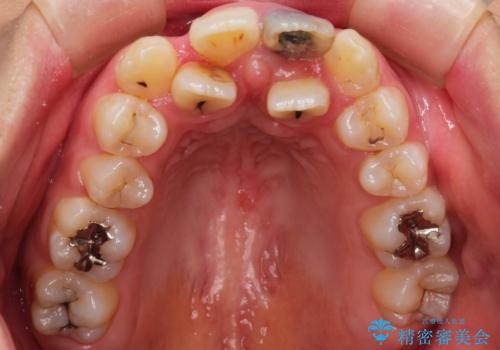

前歯が黒い セラミックで綺麗に 20代女性

- 前歯が黒くなってきたことを主訴に来院された患者様です。

精査したところ、う蝕により歯の内側から黒くなっていました。

※重度叢生のため矯正治療や機能していない歯の抜去を提案致しましたが、ご希望されませんでした。